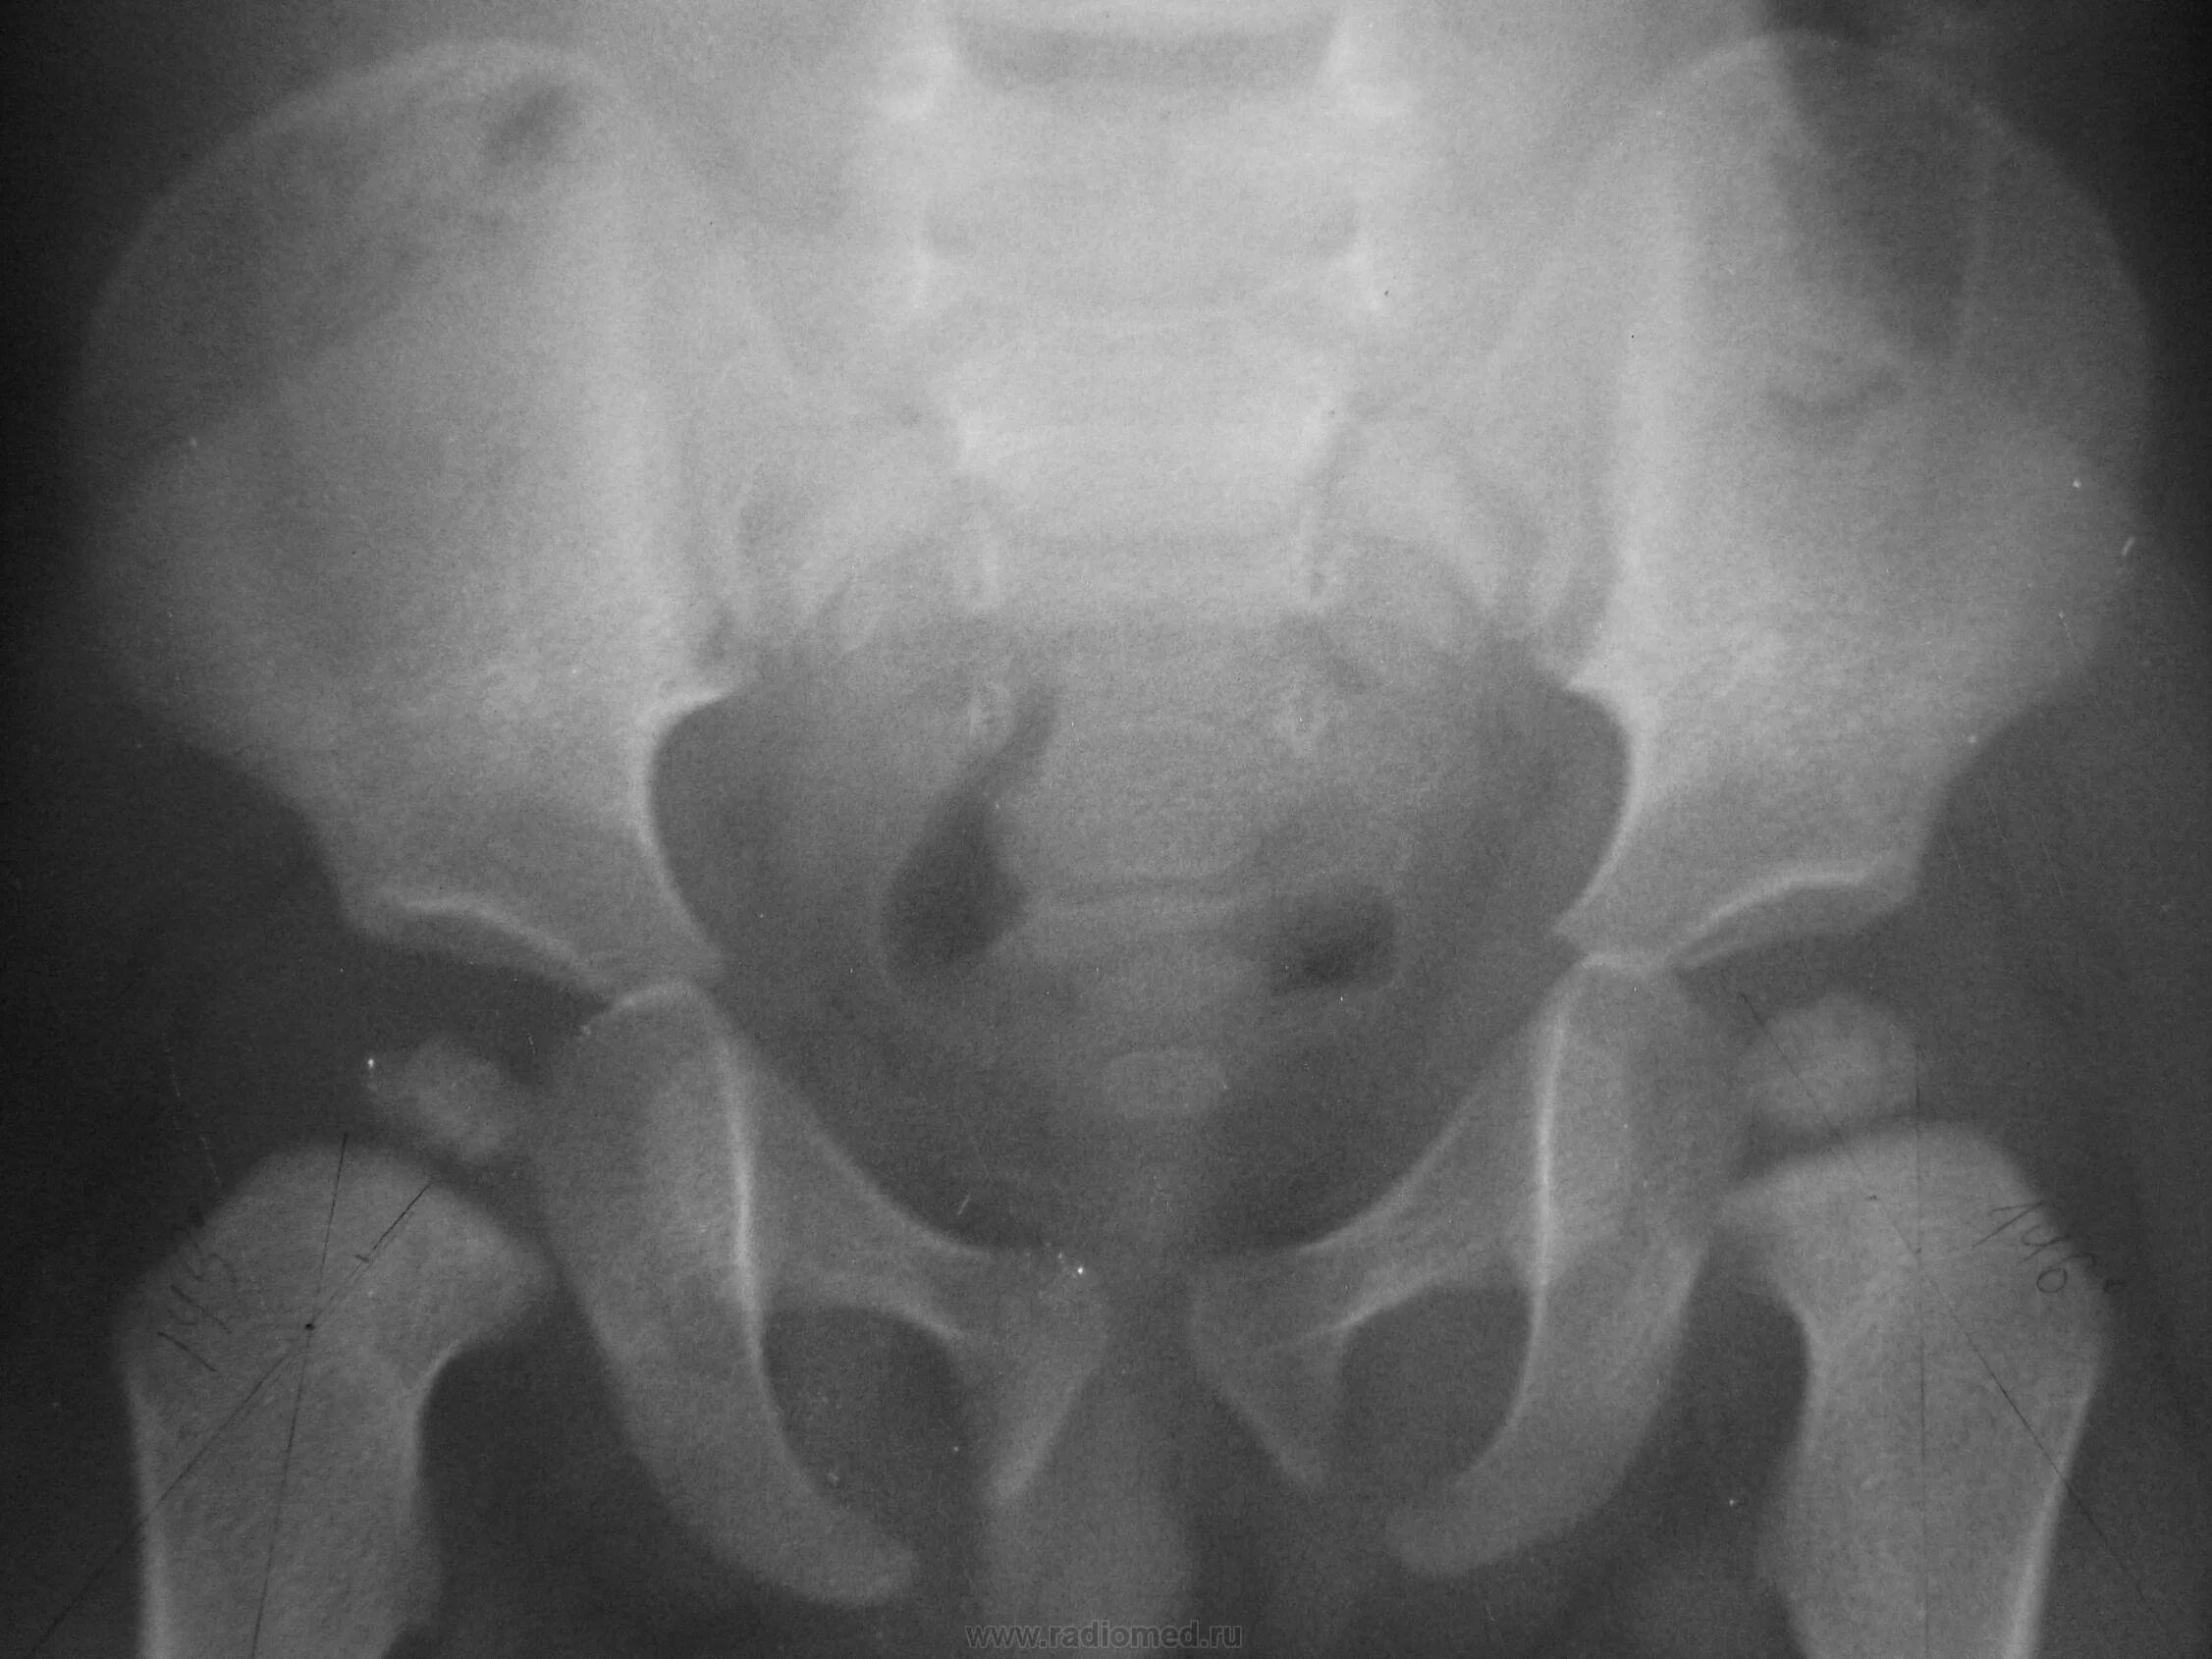

Дисплазия тазобедренного сустава мкб 10